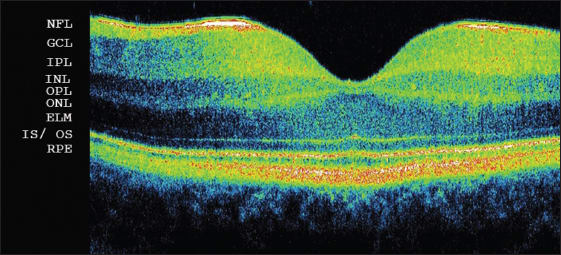

SD-OCT demonstrates high-resolution images of the retina (Figure 1), which may resemble histological dissection. Several layers, such as the nerve fiber layer, the junction between the inner and outer segments of photoreceptors, and the retinal pigment epithelium, have a high degree of backscattering, which produces highly reflective bands on SD-OCT images. The inner and outer plexiform layers have slightly more backscattering than the ganglion cell layer and inner and outer nuclear layers; thus, those structures may be differentiated.

Figure 1. Spectral-domain optical coherence tomography of a healthy fovea: NFL: nerve fiber layer; GCL: ganglion cell layer; IPL: inner plexiform layer; INL: inner nuclear layer; OPL: outer plexiform layer; ONL: outer nuclear layer; ELM: external limiting membrane; IS/OS: junction between inner and outer segments of photoreceptors; RPE: retinal pigment epithelium.